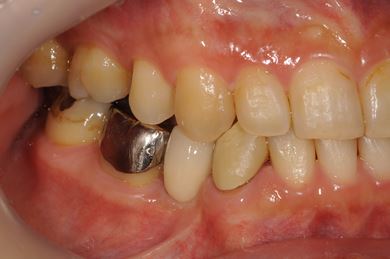

インプラントの症例写真 IMPLANT

骨再生インプラント治療

| 性別/年齢 | 男性 / 34歳 | ||||||||||||||||||||||||||||||||

| 治療方針 | ソケットリフトにて上顎洞を拳上し、インプラント治療を可能にする。 | ||||||||||||||||||||||||||||||||

| 治療内容 | インプラント1本(ソケットリフト)、メタルボンドセラミッククラウン1本 | ||||||||||||||||||||||||||||||||

| 総治療費 | 547,838円 | ||||||||||||||||||||||||||||||||

| 治療期間 | 4ヶ月 |